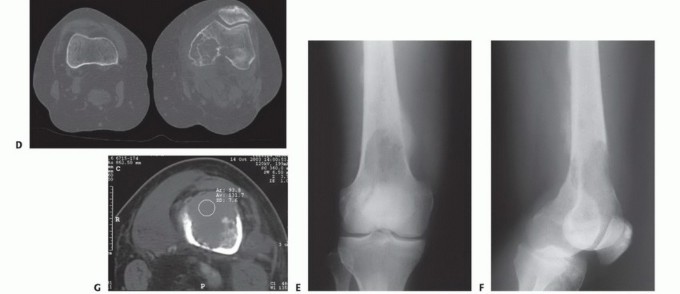

* التشخيص: يتم تشخيص الكسور المرضية عادةً من خلال الأشعة السينية، التي تظهر منطقة التلف العظمي والكسر. قد تكون هناك حاجة إلى فحوصات تصويرية إضافية مثل التصوير المقطعي المحوسب (CT) أو الرنين المغناطيسي (MRI) لتقييم مدى الضرر بشكل كامل.

* الأشعة السينية (X-ray): أول خطوة للكشف عن أي تغييرات في العظم مثل التدمير العظمي (الآفات الحالة للعظم) أو تكوين عظم جديد غير طبيعي (الآفات البانية للعظم).

* التصوير المقطعي المحوسب (CT Scan): يوفر صورًا مقطعية مفصلة للعظم والأنسجة الرخوة، مما يساعد في تحديد حجم الورم وتقييم مدى تلف العظم بشكل أدق.

* التصوير بالرنين المغناطيسي (MRI): يُعد الأفضل لتقييم الأنسجة الرخوة المحيطة بالعظم، وتحديد مدى انتشار الورم داخل نخاع العظم، والكشف عن أي ضغط على الأعصاب.